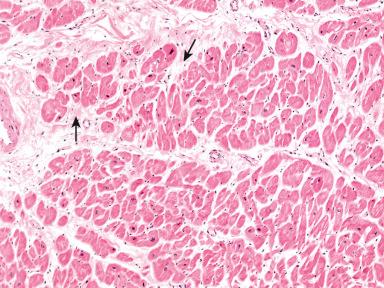

Figure 9-9, Acute myocardial ischemia.

Figure 9-10, Acute myocardial ischemia with wavy fibers.